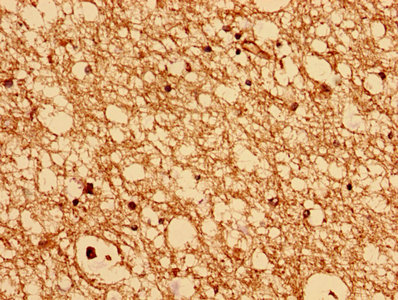

• Immunohistochemistry analysis of human brain tissue using CSB-PA846622LA01HU at dilution of 1:100